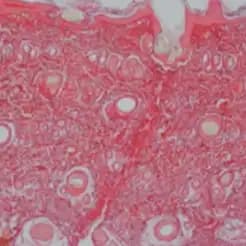

In vivo study: Histological evaluation of tissue repair. Detections using Sirius red dye and polarised light

Short Term: Hydrating and volume-enhancing action similar to HA Reorganize into a hydrophilic three-dimensional gel that binds large amounts of water with an immediate volumising effect.

Long Term: It will promote fibroblast migration and growth, Enhance protein production, enhance extracellular matrix synthesis, reduce inflammation and promote angiogenesis.